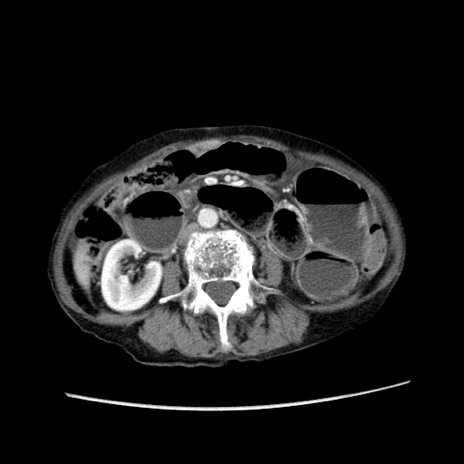

症例25(横断像)

【症例】80歳代女性

【主訴】胸のつかえ感

【現病歴】約9時間前に食後から胸のつかえた感じあり、嘔吐あり、来院。

【既往歴】胃癌(全摘)、胆摘、虫垂炎

【身体所見】心窩部に圧痛あり、反跳痛なし。

【データ】WBC 5700、CRP 0.05